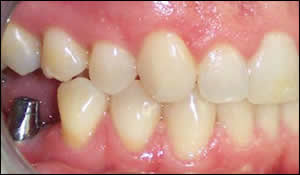

Fig 5: An intraoral view of the implant abutment.